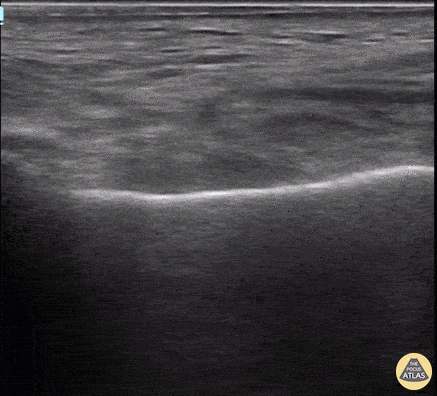

A female patient with a history of Non-Hodgkin and Diffuse B-Cell Lymphoma presented for evaluation of subacute facial swelling. Physical exam revealed edema over the parotid gland without associated tenderness to palpation. POCUS seen here demonstrated hypoechoic and septated cystic lesions within the parotid gland, concerning for malignancy. This finding prompted further evaluation with CT that confirmed recurrence of malignancy. Lydia Mansour, DO, PGY2 Central Michigan University Emergency Medicine Resident